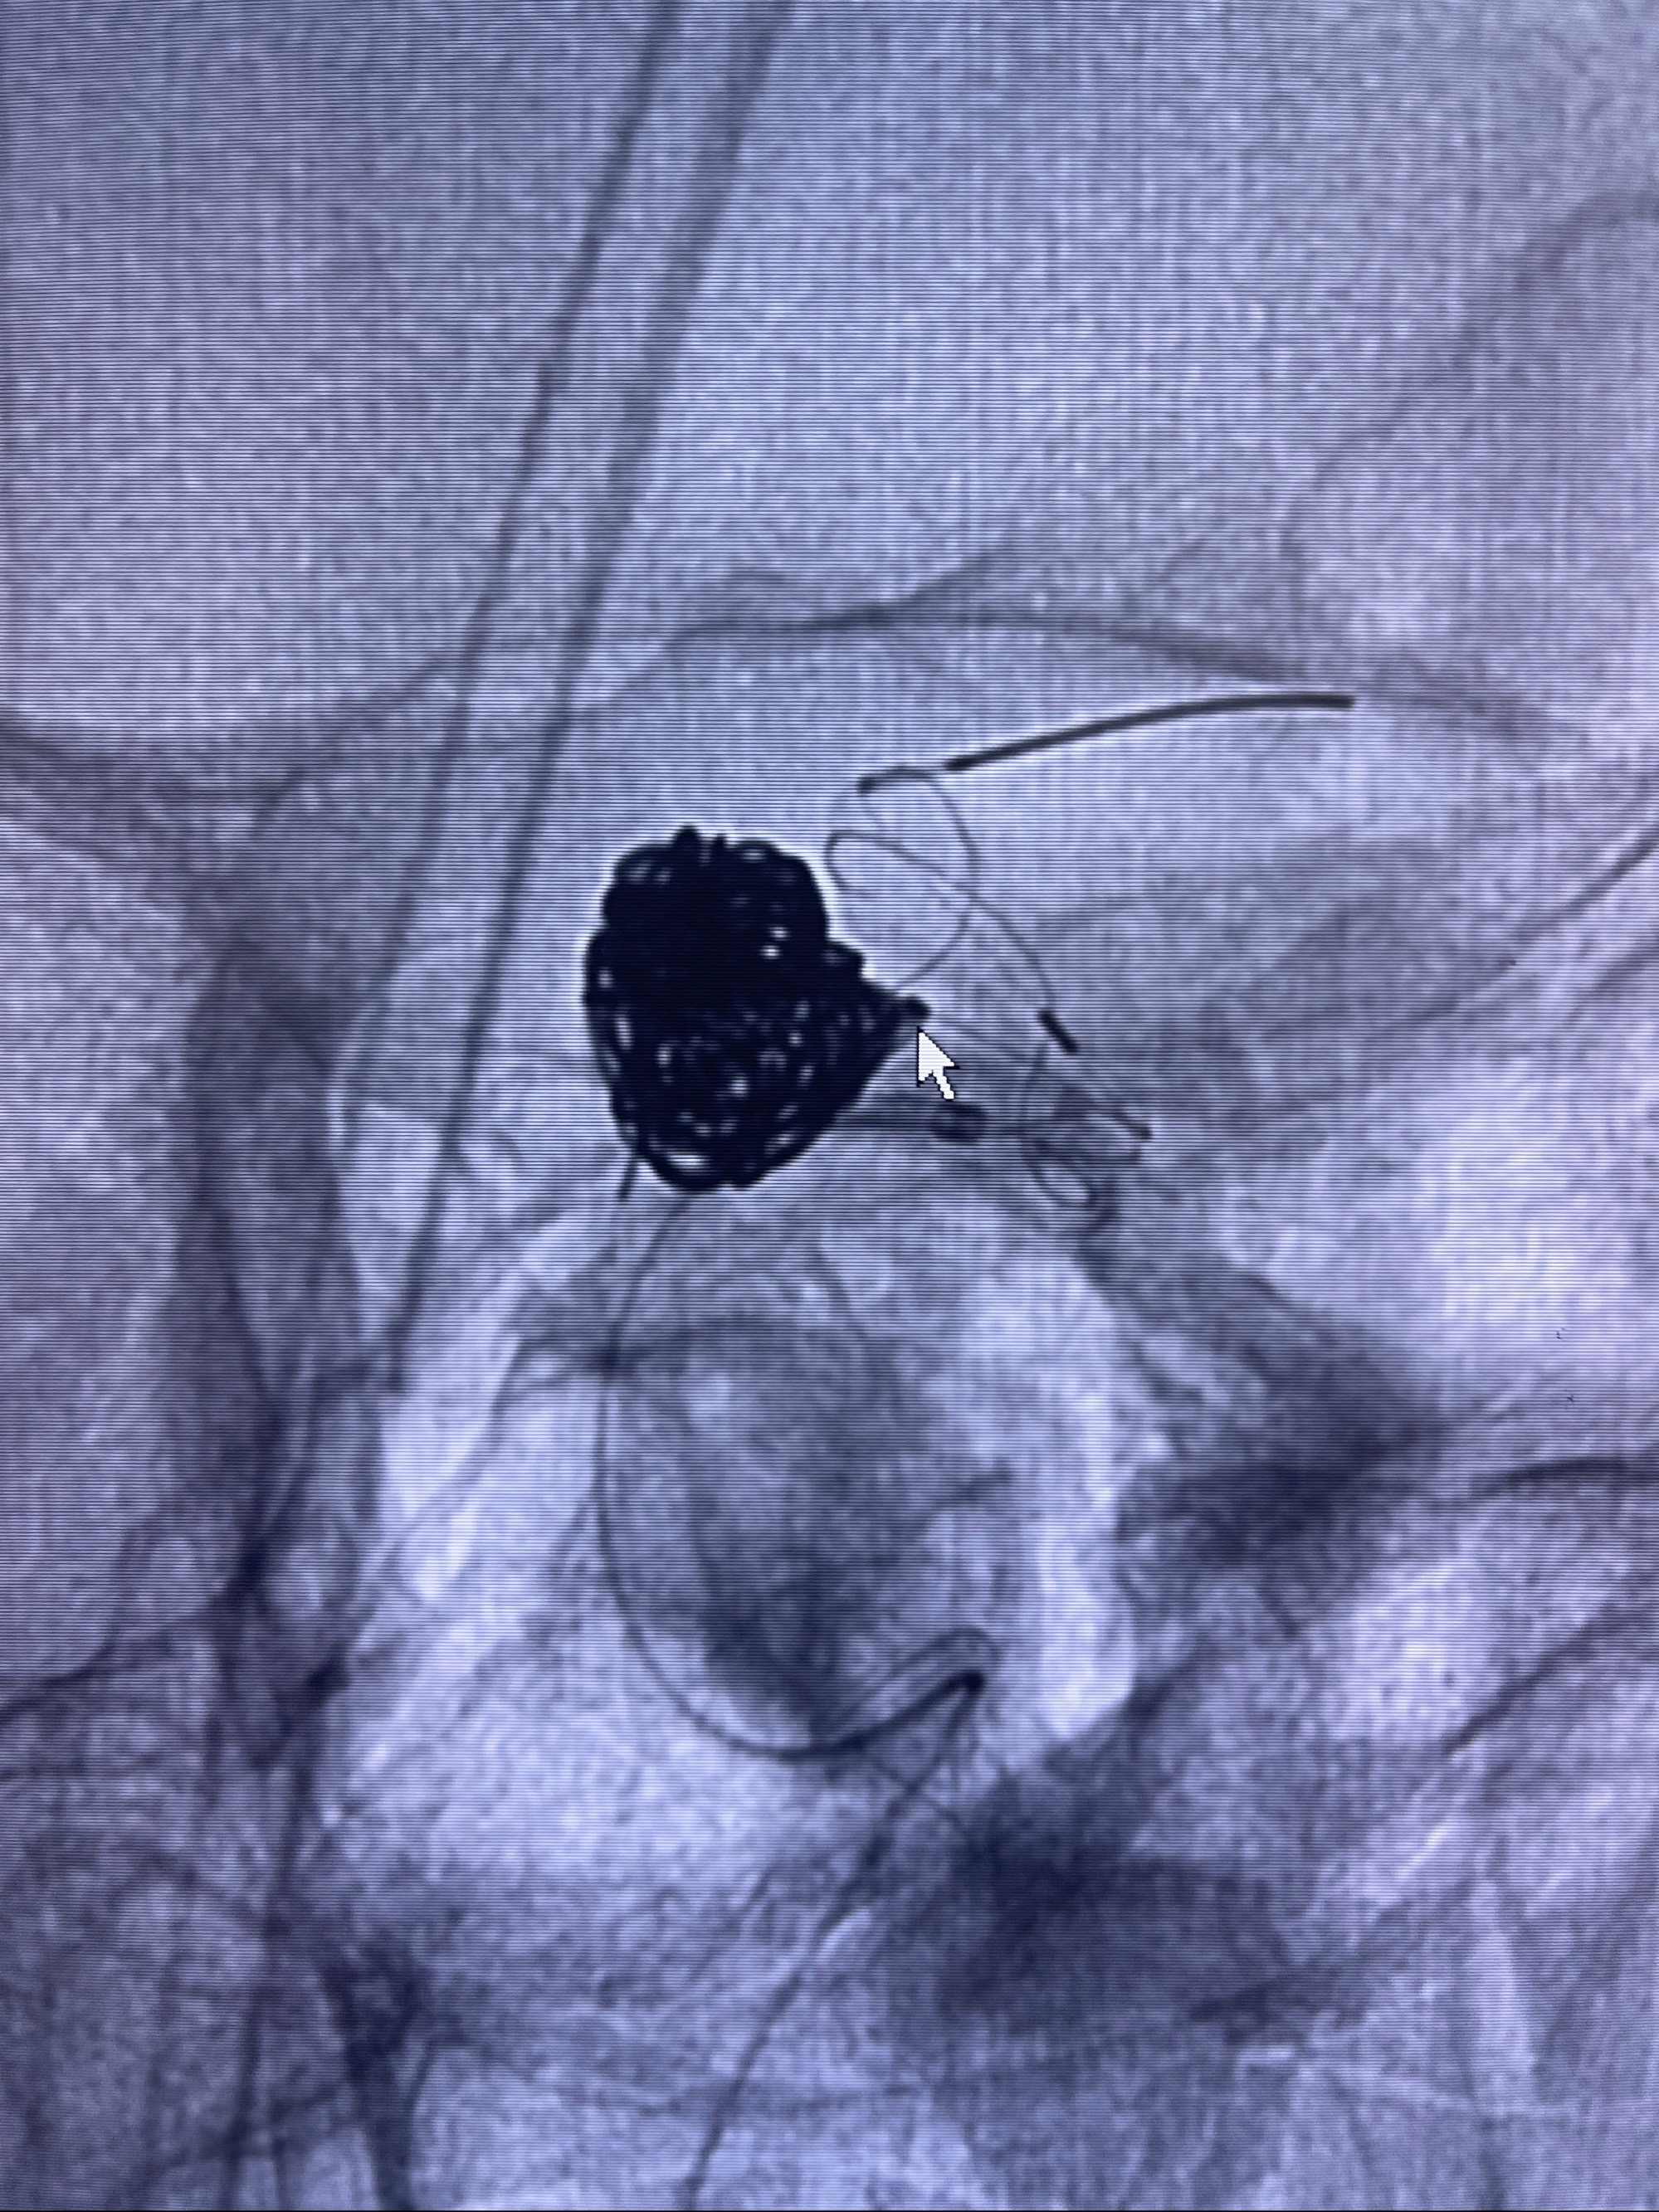

2023-08-30DSA:左侧颈内动脉眼动脉动脉瘤,约3*9.2*7.3mm大小

密网支架辅助栓塞

- Tubridge 4.0-20mm密网支架

- 加奇微弹簧圈:7*30/6*20/5*20/2*8

术后3D显示支架贴壁佳